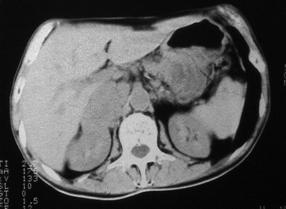

Fig.4. Feocromocitom suprarenalian stâng - aspect TC. |